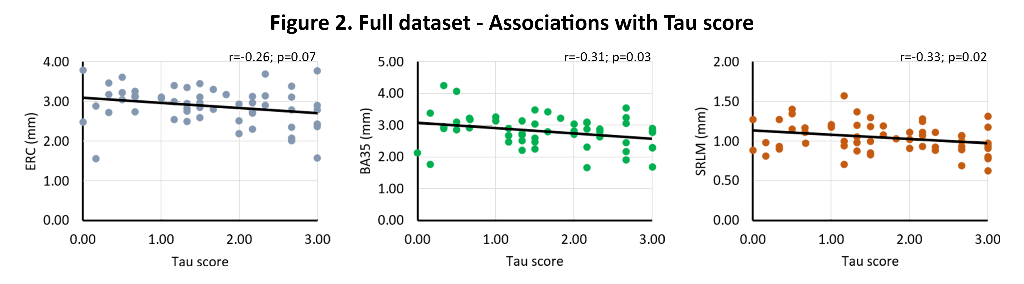

Tau, TDP-43, β-amyloid and α-synuclein pathology were rated (0-absent – 3-frequent) in the hippocampus and entorhinal cortex (ERC) of 58 individuals with and without neurodegenerative diseases (mean age 74.7 years, 39.7% female). Thickness measurements using a semi-automated approach were obtained from 0.2x0.2x0.2 mm3 post-mortem MRI scans of excised MTL specimens from the contralateral hemisphere in the ERC, Brodmann Area (BA) 35 and 36, parahippocampal cortex (PHC), subiculum (SUB), cornu ammonis (CA)1 and the stratum radiatum lacunosum moleculare (SRLM). Spearman’s rank correlations were performed, correcting for age, sex and hemisphere, including all four proteinopathies in the model.

We find significant associations of 1) TDP-43 with all subregions (r=-0.27 – r=-0.46, trend for subiculum), and 2) tau with ERC (r=-0. 26, trend), BA35 (r=-0.31) and SRLM (r=-0.33). In β-amyloid and TDP-43 negative cases, we find strong significant associations of tau with ERC (r=-0.40, trend), BA35 (r=-0.55), subiculum (r=-0.42), CA1 (r=-0.47) and SRLM (r=-0.38, trend). See figures 1-3.

This unique dataset showed widespread atrophy in relation to TDP-43 pathology and atrophy in early Braak regions and tau pathology. Moreover, the strong association of tau with thickness in early Braak regions in the absence of β-amyloid and TDP-43 is indicative for a role of Primary Age Related Tauopathy in neurodegeneration.